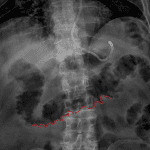

Age: 87

Sex: Male

Indication: Confirm feeding tube placement

Findings

- Feeding tube tip overlies the gastric fundus

- Mural thickening of the transverse colon with thumbprinting

- Nonobstructive bowel gas pattern

- Surgical clips overlie the anatomic pelvis

- Mild streaky bibasilar pulmonary opacities

Diagnosis

- Colitis due to C. dificile

Feeding tube tip overlies the gastric fundus. Recommend advancement if postpyloric placement is desired.

Mural thickening of the transverse colon concerning for colitis, which could be infectious (to include C. dificile) or inflammatory in etiology.

Nonobstructive bowel gas pattern.

Mild streaky bibasilar pulmonary opacities, which likely represent atelectasis. Consider dedicated chest radiographs for further evaluation.